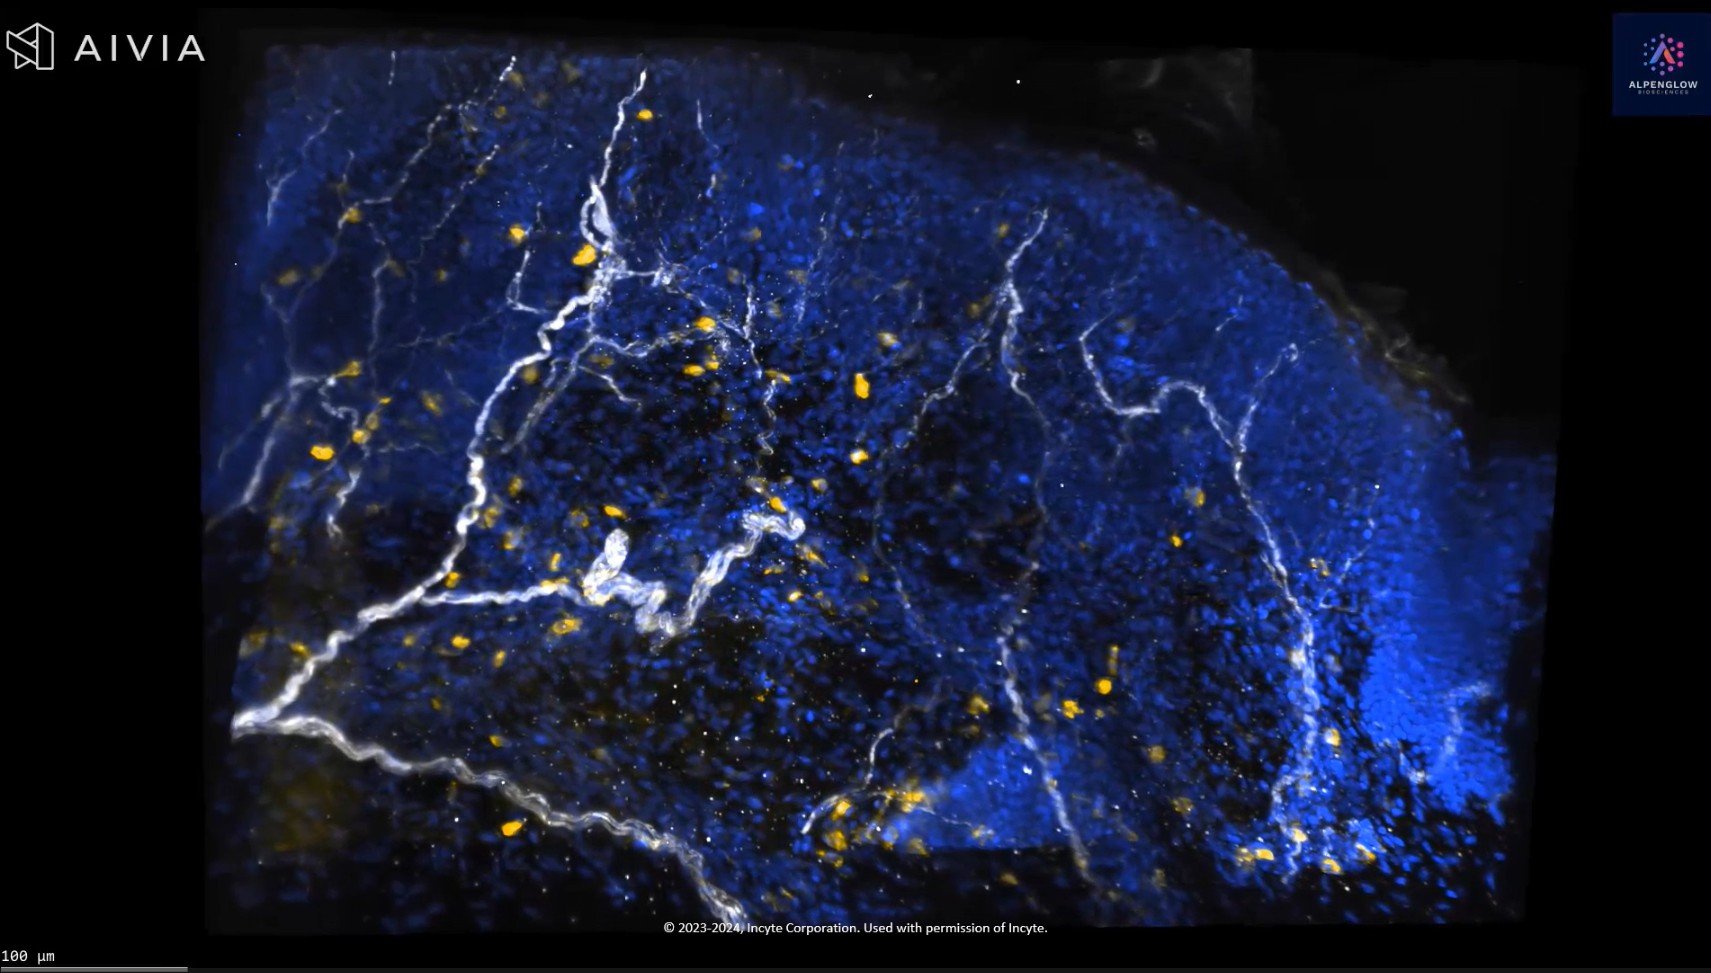

CD45 staining in whole skin biopsy

CD45 staining in whole skin biopsy captured through advanced 3D imaging.

Explore the dynamic interplay of lymphocyte distribution around the nerve network and the complex cellular architecture of the skin.

Appreciate the result of precise data management and image segmentation that unveils lymphocyte distribution around nerves with remarkable accuracy.

Lymphocytes Cluster Near Nerves in Atopic Dermatitis

Delve into the intricate details of a lesional atopic dermatitis sample captured with cutting-edge 40X high-resolution 3D imaging. The sample is vividly stained with TO-PRO-3 blue for nuclei, PGP 9.5 white for nerves, and CD45 yellow for lymphocytes. Marvel at the precise preservation of epidermal and dermal structures and the clear visualization of immune-cell clusters in close proximity to specific nerve fibers.